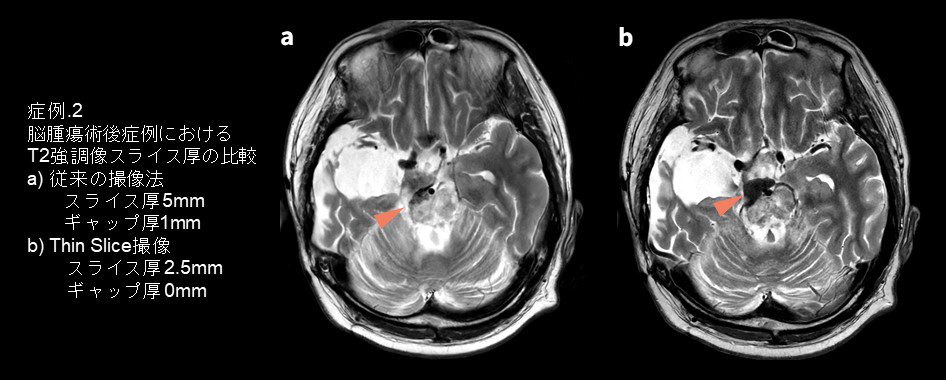

・症例2

神経膠腫の摘出および放射線治療後の症例です。T2強調像のAxial撮像で、従来の撮像法(スライス厚5mm・ギャップ厚1m)とThin slice撮像(スライス厚2.5mm・ギャップ厚0mm)を比較しました。放射線治療により壊死した腫瘍の一部が繊維化しており、T2強調像で低信号に描出されています。やはり一目でスライス厚が薄いほうがくっきりと描出されており、病変範囲が分かりやすくなっています。症例1と同様に、従来はノイズや撮像時間の関係から気軽にはthin slice化することは困難だったのですが、AIR™ Recon DLを活用することでthin sliceにしても2分弱での撮像が可能なため、日常臨床での活用が格段に容易になりました。